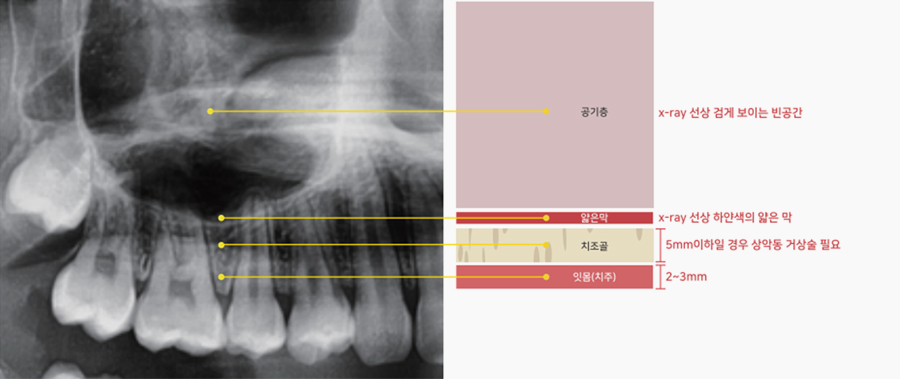

심 : 특화진료상악동이란 위턱뼈 속 공기가 차있는 비어있는 공간입니다.

얇은막으로 쌓여있으며 상악골의 대부분을 차지하는 가장 큰 공간입니다.

상악동은 얇은막으로 씌여진 공기주머니 형태로 그 위에 감싸진 뼈의 안쪽에 위치하고 있습니다.

치조골의 양이 임플란트 식립 조건에 충족되지 못한 상태에서 임플란트가 식립될 경우 임플란트의 유지가 힘듭니다.

그렇기 때문에 상악동을 들어올려 뼈를 이식한 공간을 확보 후 뼈를 이식하는 것이 상악동 거상술 입니다.

임플란트를 심으려면 최소 5~7mm의 뼈폭이 확보되어야 합니다.

치조골이 녹아 치조골의 높이가 5~7mm이하일 경우 상악동을 들어올리는

상악동거상술을 시행한 뒤 그 빈공기층 안에 뼈이식을 해야합니다.